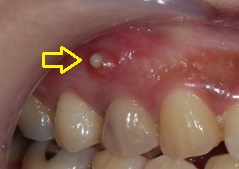

잇몸에 생긴 구멍을 전문 용어로 누공(瘻孔、ろうこう)이라고 합니다.

영어로는 Fistula 혹은 Sinus tract라고도 하고요.

여하튼 누공은 분명 정상적인 현상이 아닙니다.

잇몸에 구멍이 생겼다고 하면, 분명 그 구멍 내부에는 비정상적인 문제가 있기 때문이죠.

혓바닥으로 누공 근처를 대보면, 대개 씁쓸한 맛이 느껴지는 경우가 많은데요.

이런 씁쓸한 맛의 정체는 바로 염증물입니다.

아래 이미지를 참고하시면 이해가 더 빠를 것 같습니다 ㅎㅎ